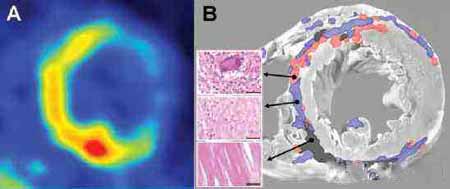

5、引发心脏病:研究数据显示,类风湿性关节炎并发心包炎的机率高达20%~50%,少数形成的无症状类风湿结节,往往在心脏超声检查时会发现。另外,还有相当一部分患者会出现左心衰竭的情况。